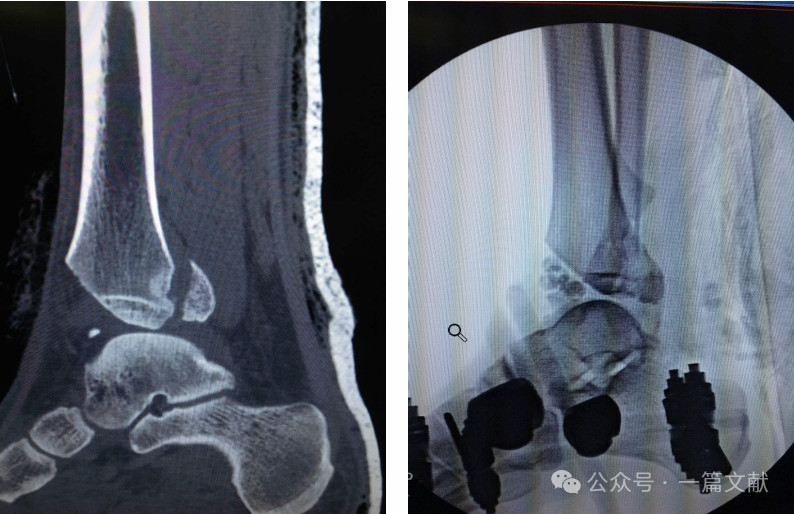

11.4 二次手术行逆行胫距跟关节(TTC)髓内钉固定的关节融合术。如下图:

关节面缺损:

一期行踝关节融合术: